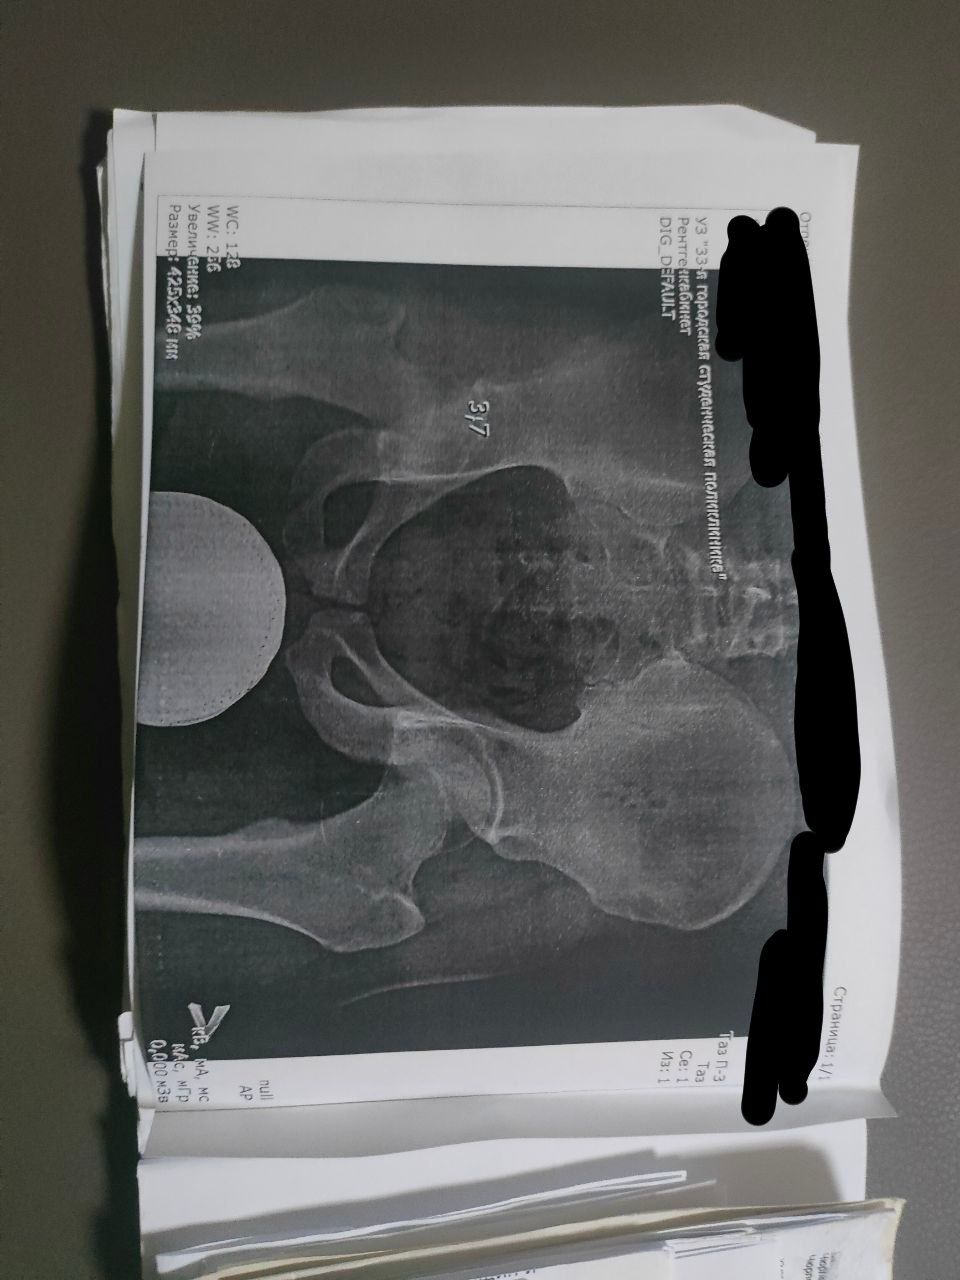

Здравствуйте,могу ли рассчитывать на категорию годности В по коксартрозу или категории годности Д по полой стопе.

1. По коксартрозу присвоят призывную категорию годности "Б-3" по статье 65, пункту "г" Расписания болезней, так как он не сопровождается нарушением функций сустава в виде нестабильности и (или) контрактуры (ограничения амплитуды движений).